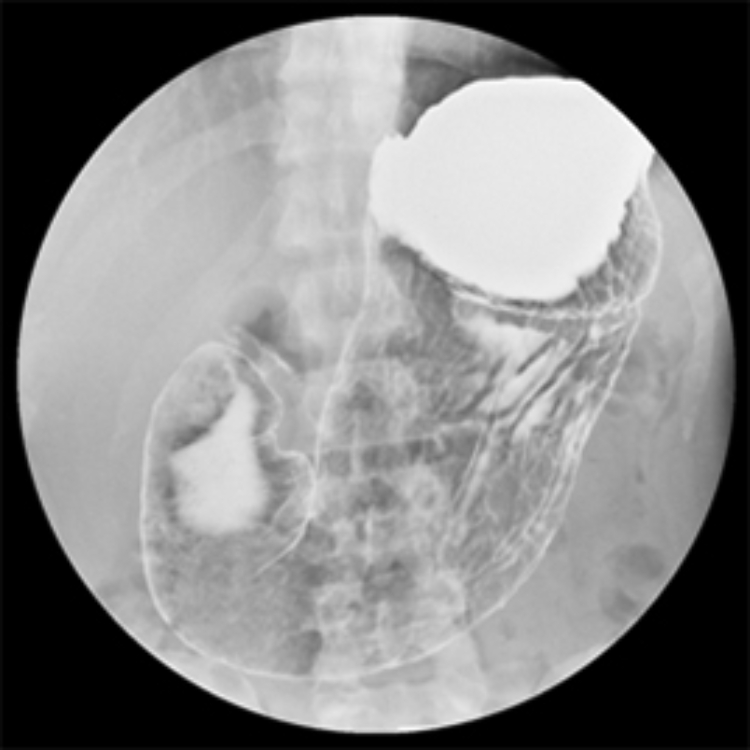

胃透視検査(バリウム検査)

バリウムを飲んで胃の形や粘膜の凹凸を確認します。

検診などで行われることが多いですが、内視鏡よりも精度は劣ります。